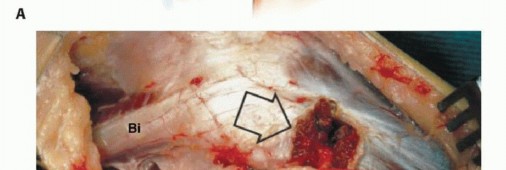

الكشط (Curettage):

- الإشارة: يُستخدم للأورام الحميدة العدوانية والأورام الغرنية منخفضة الدرجة المرتبطة بتدمير قشري بسيط وامتداد خارج العظم ضئيل.

- الإجراء: يتم إزالة الورم يدويًا بواسطة مكشطة، ثم تُستخدم مثقاب عالي السرعة لتنظيف جدران تجويف الورم بدقة لضمان إزالة أي مرض مجهري متبقي.

- الحفاظ: يتم الحفاظ على العصب الشظوي المشترك والأوعية الدموية.